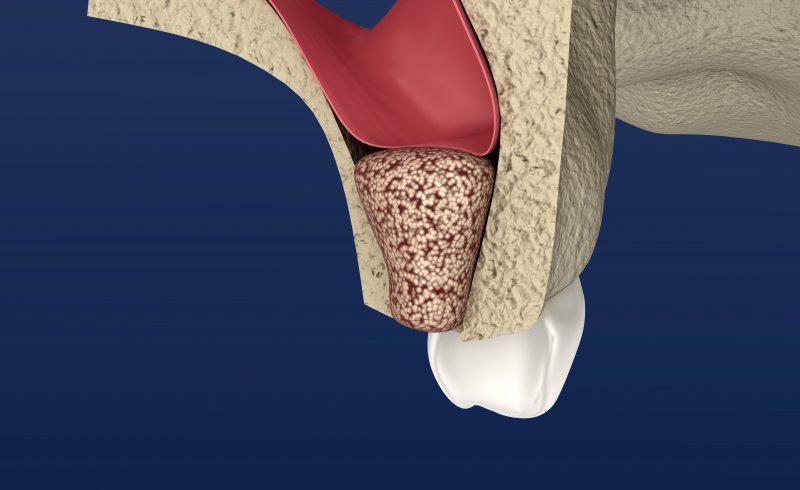

If you’ve lost all your natural teeth, don’t settle for anything less than the best. If you are ready to add the support of

If you’ve lost all your natural teeth, don’t settle for anything less than the best. If you are ready to add the support of